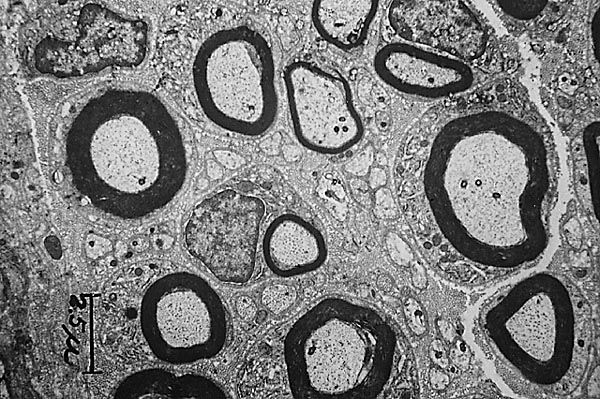

2. Oligodendrocitos

1. C. de Schwann

1. C. Satélite